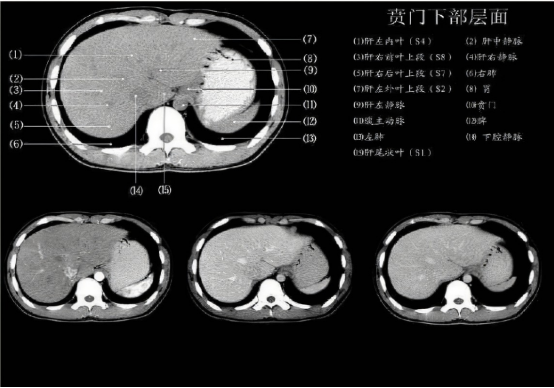

"这不是减肥,是慢性自杀!"广州医科大学附属医院内分泌科主任展示的病例CT片显示,长期服用减肥药患者的内脏脂肪反而增加23%,肌肉量流失37%。其团队研究发现,违规药物会导致: